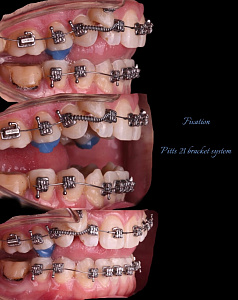

Гегиров Амир Артурович (@amir__ortodont)

Врач-ортодонт

#repost от @amir__ortodont

Была проведена полная фиксация брекетов на обе челюсти, установлены дуги и дополнительные элементы для запуска контролируемого перемещения зубов. Уже с первых месяцев лечения начинается работа над выравниванием зубных рядов, подготовкой места для правильного положения клыков и коррекцией прикуса.

В данном случае наблюдается выраженный дефицит места для клыков, поэтому лечение будет проходить поэтапно и с использованием дополнительной опоры. Каждый элемент системы работает на прогнозируемый и максимально эффективный результат.

Была проведена полная фиксация брекетов на обе челюсти, установлены дуги и дополнительные элементы для запуска контролируемого перемещения зубов. Уже с первых месяцев лечения начинается работа над выравниванием зубных рядов, подготовкой места для правильного положения клыков и коррекцией прикуса.

В данном случае наблюдается выраженный дефицит места для клыков, поэтому лечение будет проходить поэтапно и с использованием дополнительной опоры. Каждый элемент системы работает на прогнозируемый и максимально эффективный результат.